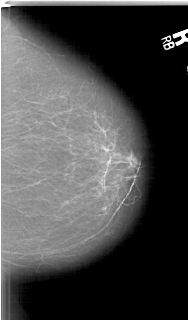

A_1627_1.RIGHT_MLO

RIGHT_CC LINES 6076 PIXELS_PER_LINE 3556 BITS_PER_PIXEL 12 RESOLUTION 43.5 NON_OVERLAY

FILE: A_1627_1.LEFT_CC.OVERLAY

TOTAL_ABNORMALITIES 1

ABNORMALITY 1

LESION_TYPE MASS SHAPE IRREGULAR MARGINS ILL_DEFINED

ASSESSMENT 4

SUBTLETY 2

PATHOLOGY MALIGNANT

TOTAL_OUTLINES 1

BOUNDARY